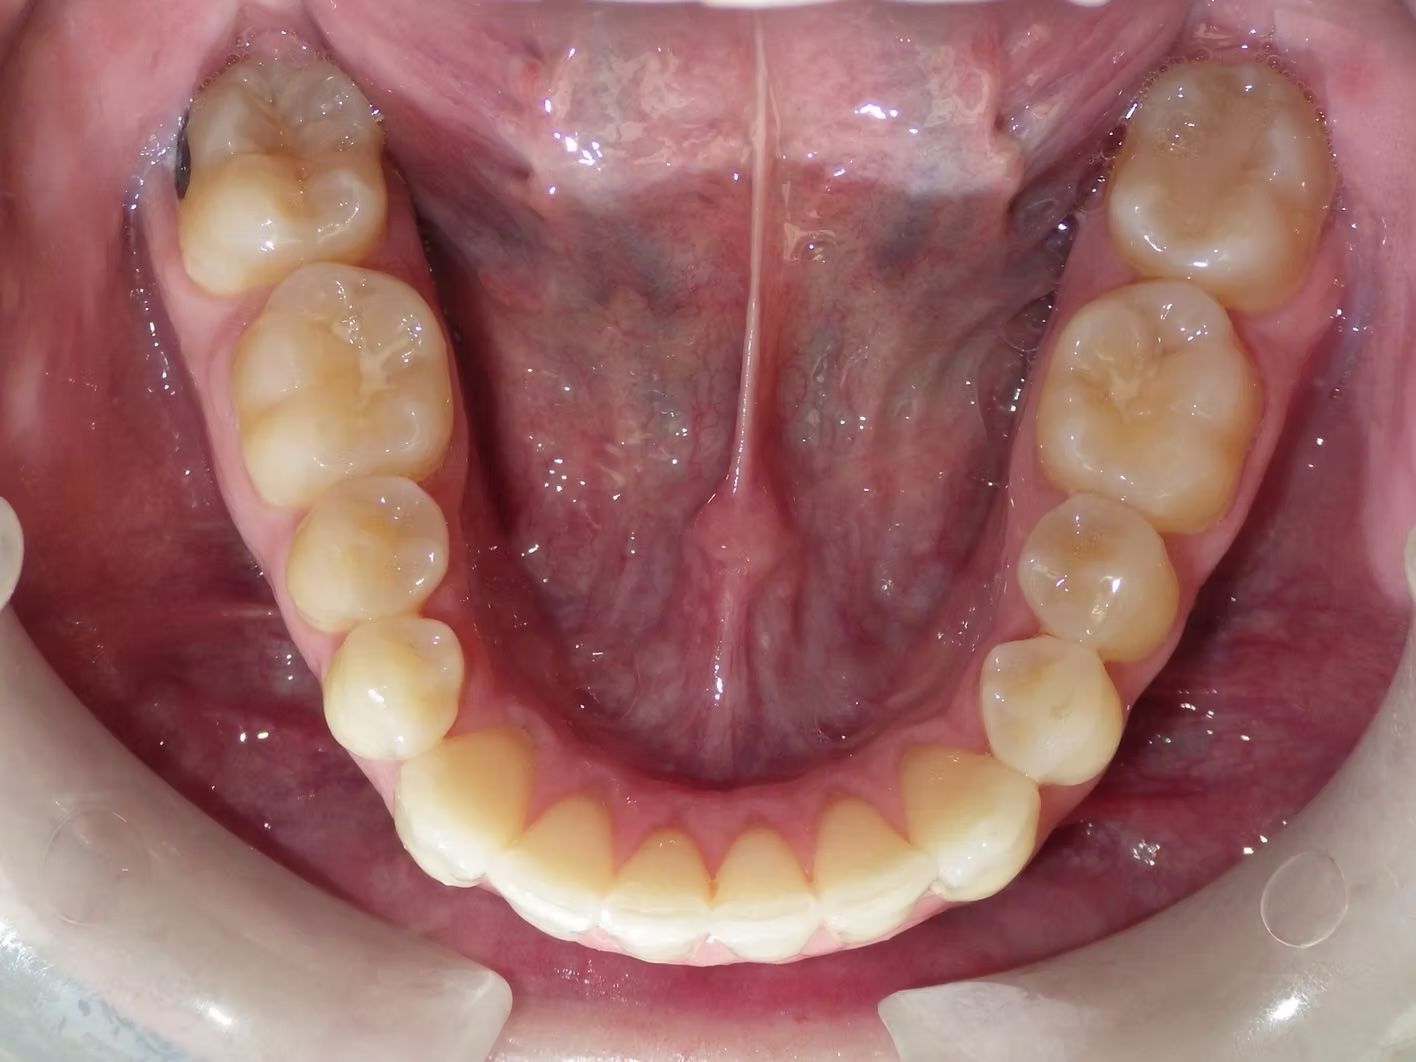

IAN

Ian came to the office because his lower teeth were crowded and he had an anterior cross bite. With traditional braces we resolved the crowding and aligned the teeth without causing flaring of the incisors and giving him a handsome smile. The treatment lasted 18 months and the final photos are at a 2 year follow up when we made him a new clear retainer.